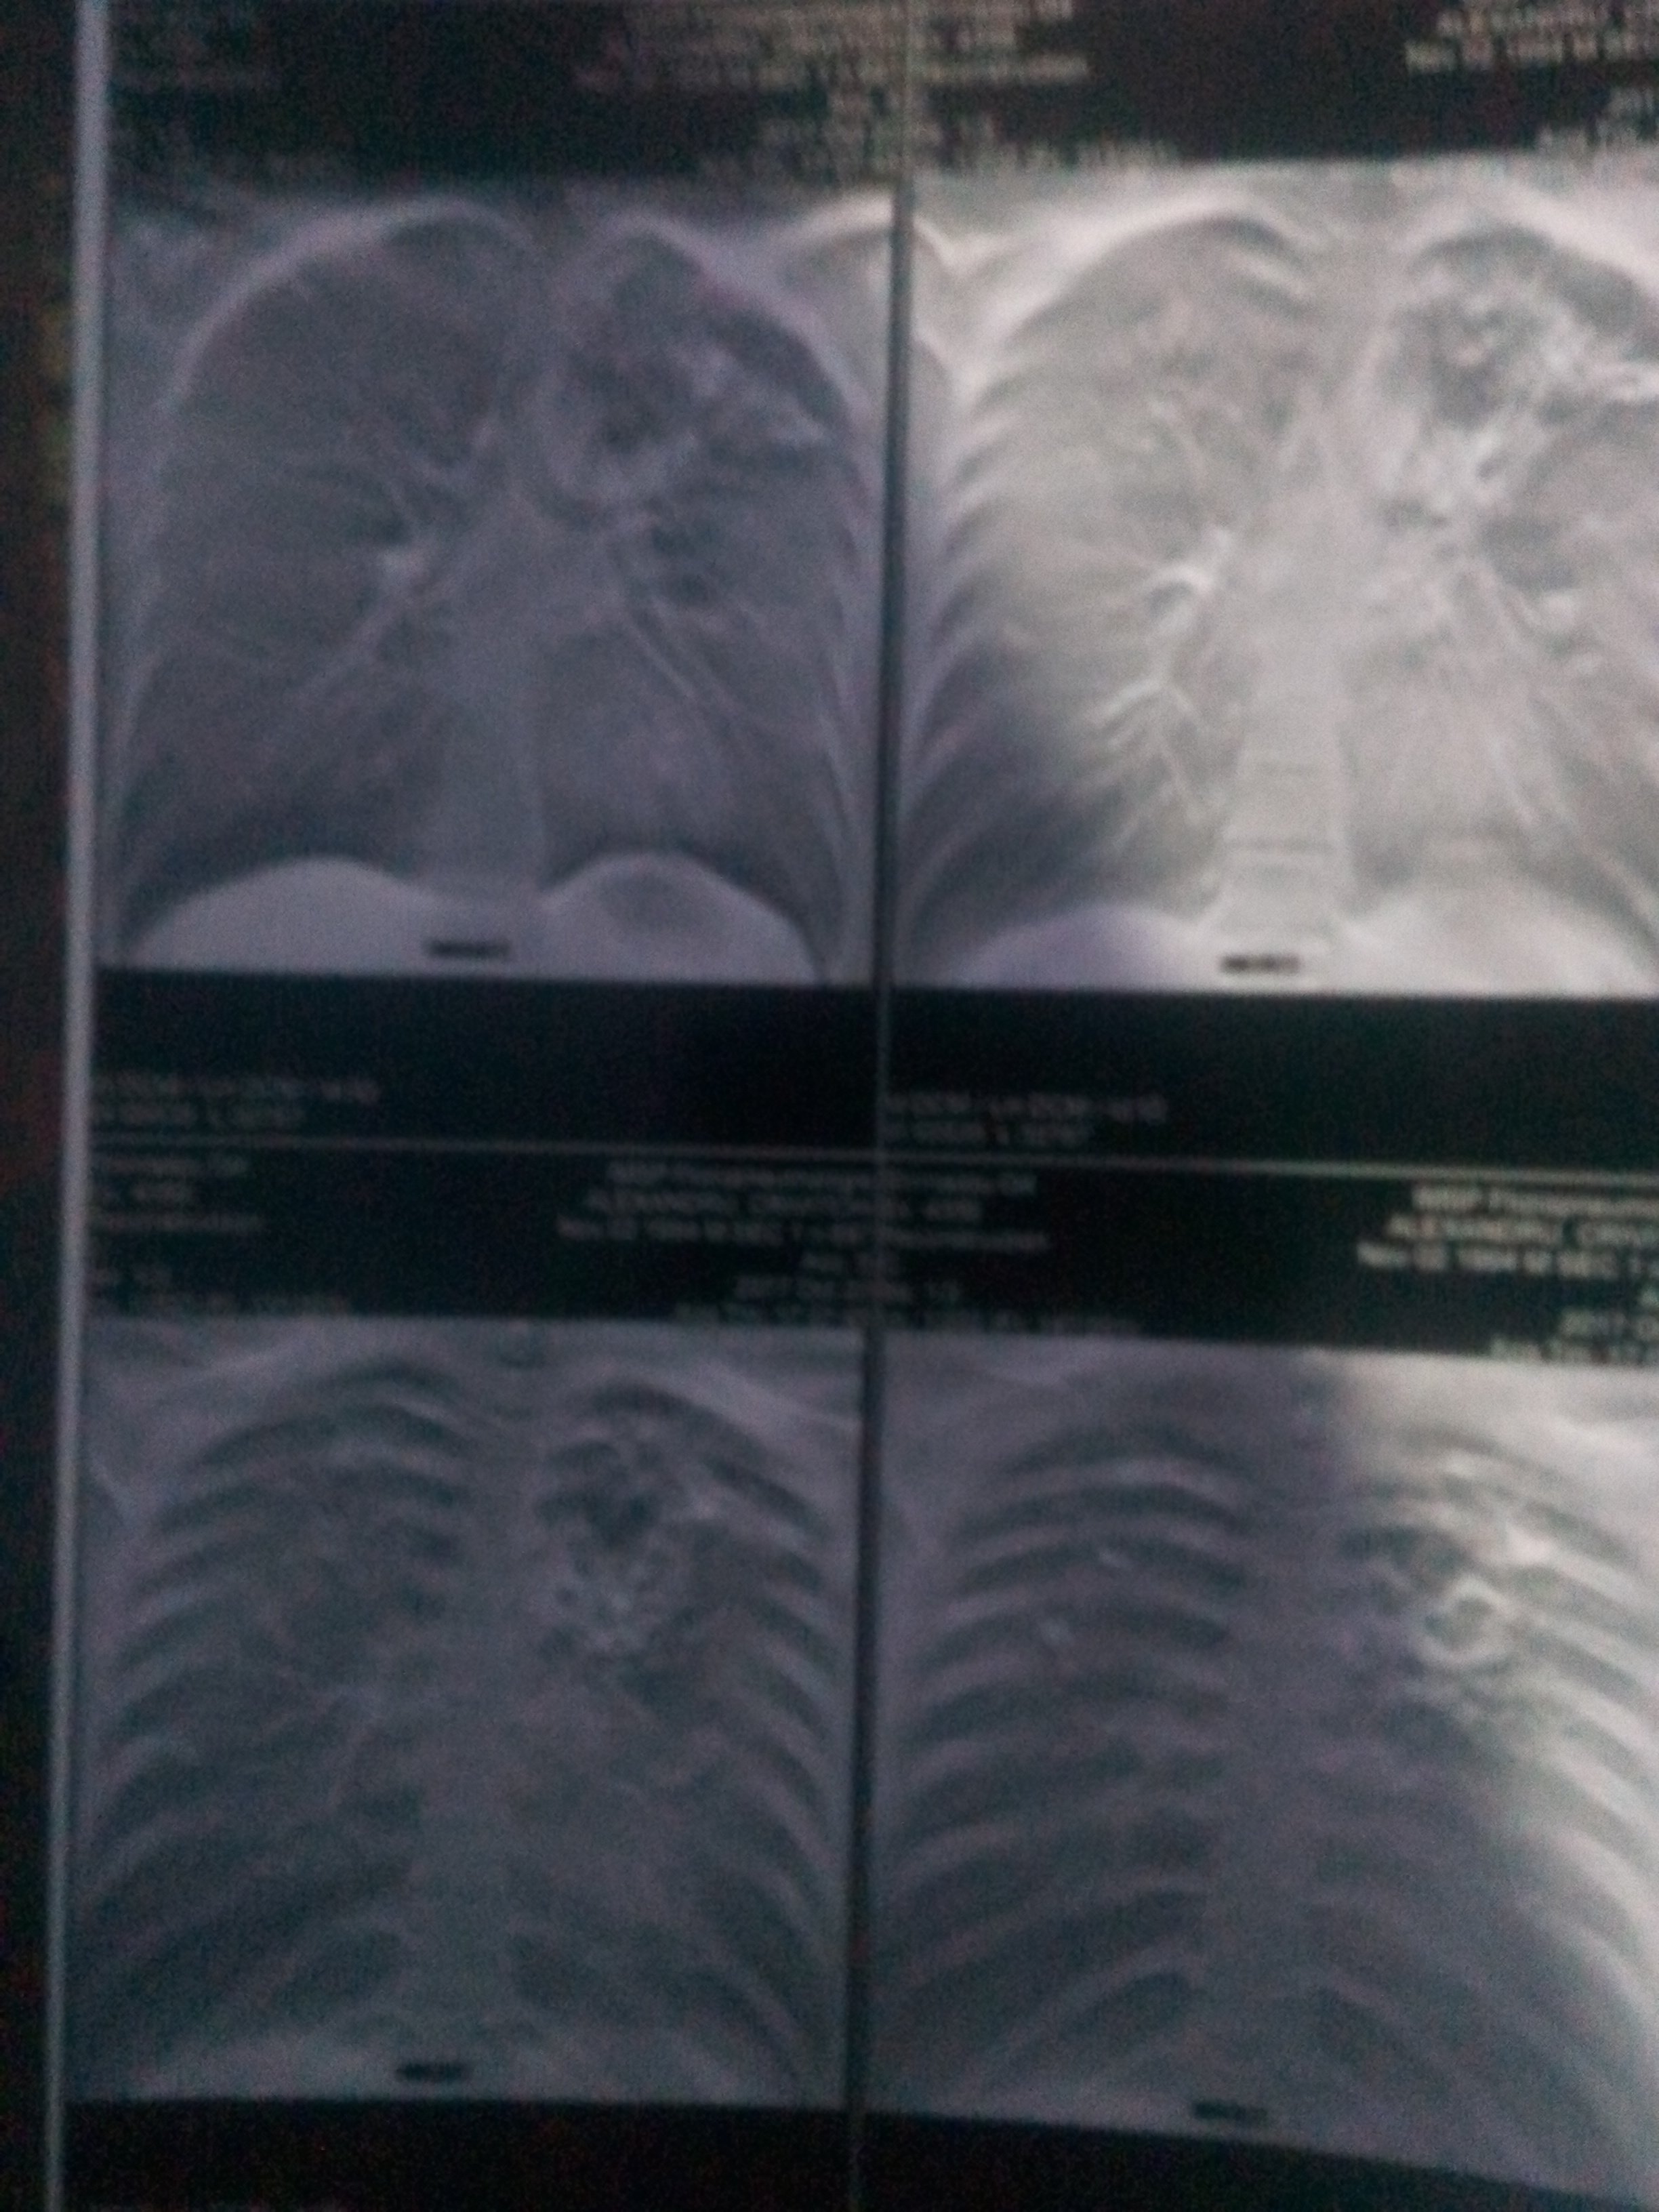

• Diagnostic: Tuberculoză pulmonară bilaterală

Sunt Alexandru Crivițchi și am 23 de ani. În luna octombrie 2017 după un an de cancer pulmonar pe care l-am învins, am fost diagnosticat cu tuberculoză pulmonară bilaterală - un diagnostic care m-a lăsat fără rude, prieteni și cunoștințe.

La data de 22 octombrie 2017 am fost internat în Spitalul de Ftiziopneumologie din Chișinău cu diagnosticul de „Tuberculoză Pulmonară Bilaterală”. Boala mi-a afectat ambii plămâni. Calvarul pentru mine a început în clipa în care am aflat diagnosticul şi de atunci încerc să mă descurc de unul singur. Acum stau în chirie în capitală și următoarele 6 sau 8 luni voi continua tratamentul antituberculos și nu pot merge la muncă. Vin cu o rugăminte către oamenii cu sufletul mare: o mână de ajutor pentru mine va fi încă o treaptă spre tratament și o viață sănătoasă. Nu vreau nimic mai mult, vreau doar să fiu sănătos. Vă rog să mă ajutați să pot trăi. Mulțumesc!